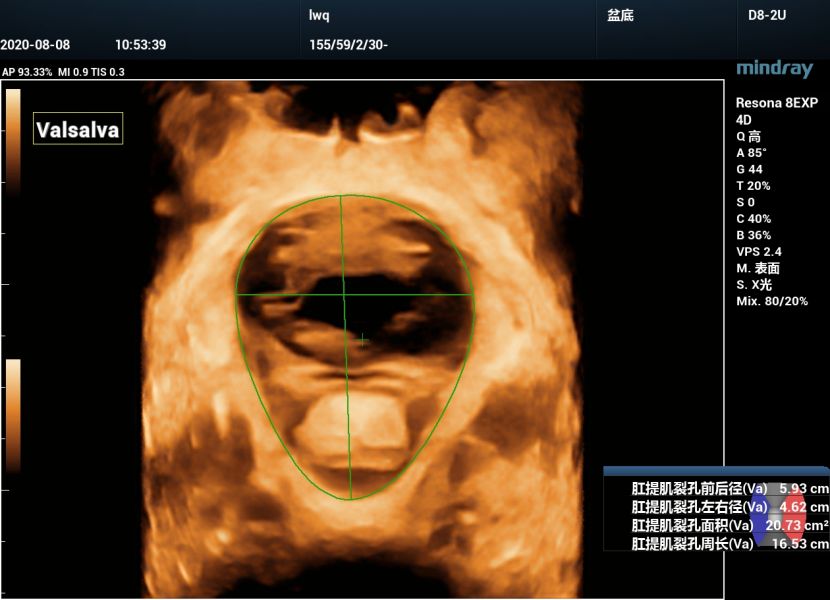

生殖裂孔面积及前后径